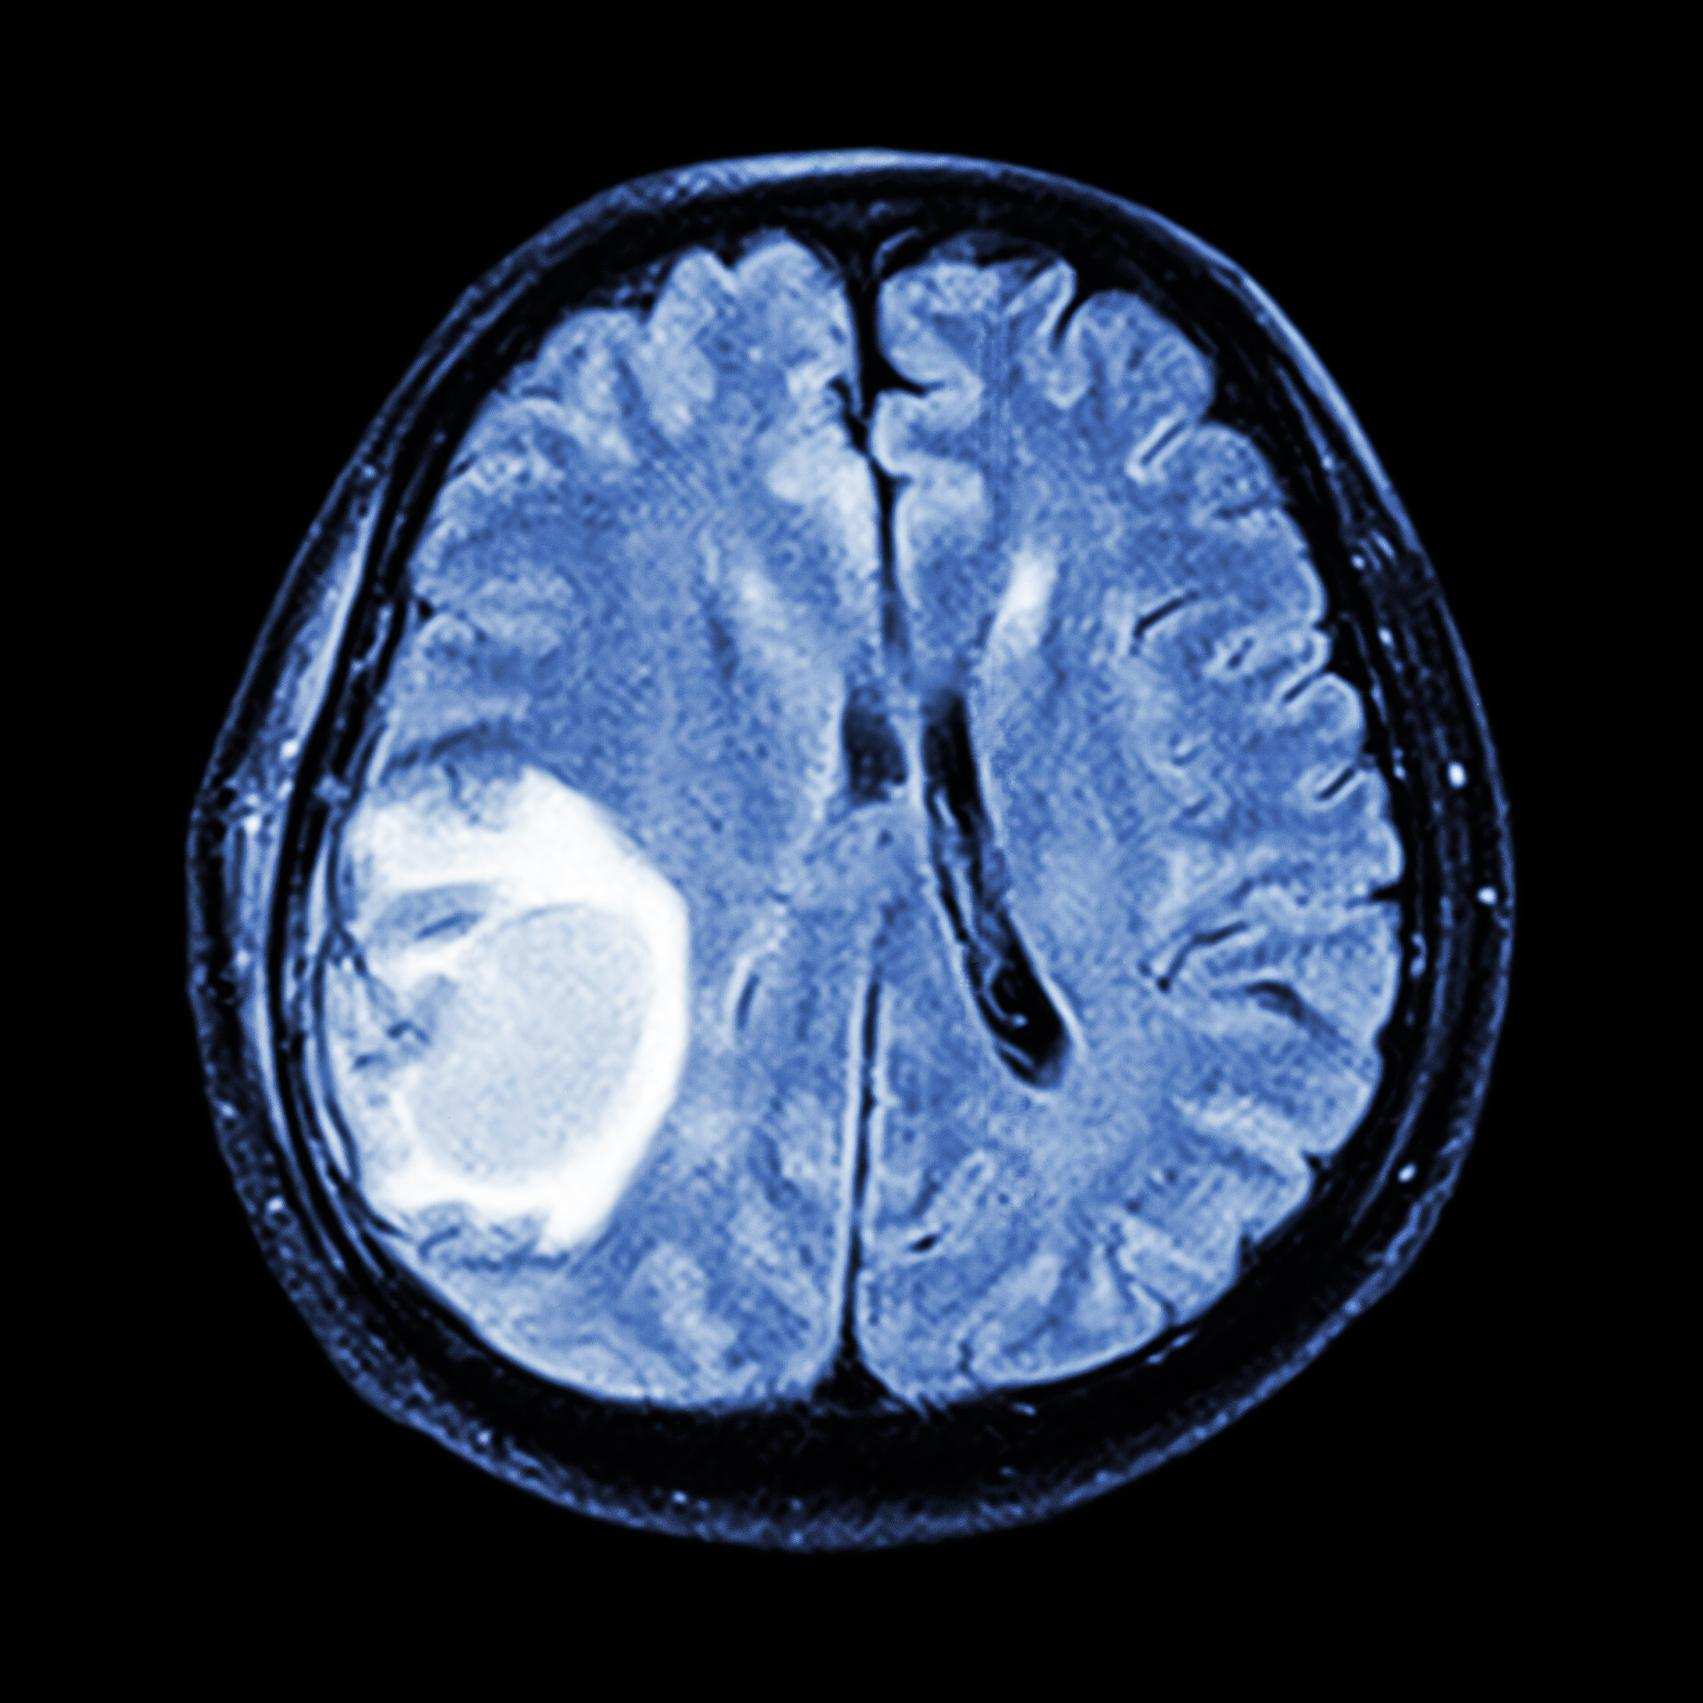

Ученые нашли метод борьбы с неизлечимым раком мозга

Специалисты из Международной школы продвинутых исследований создали метод генной терапии, которая окажет эффективную помощь в лечении одного из видов агрессивной раковой опухоли мозга — глиобластомой. Результаты работы опубликованы в медицинском издании Oncotarget, пресс-релиз размещен на сайте SISSA.